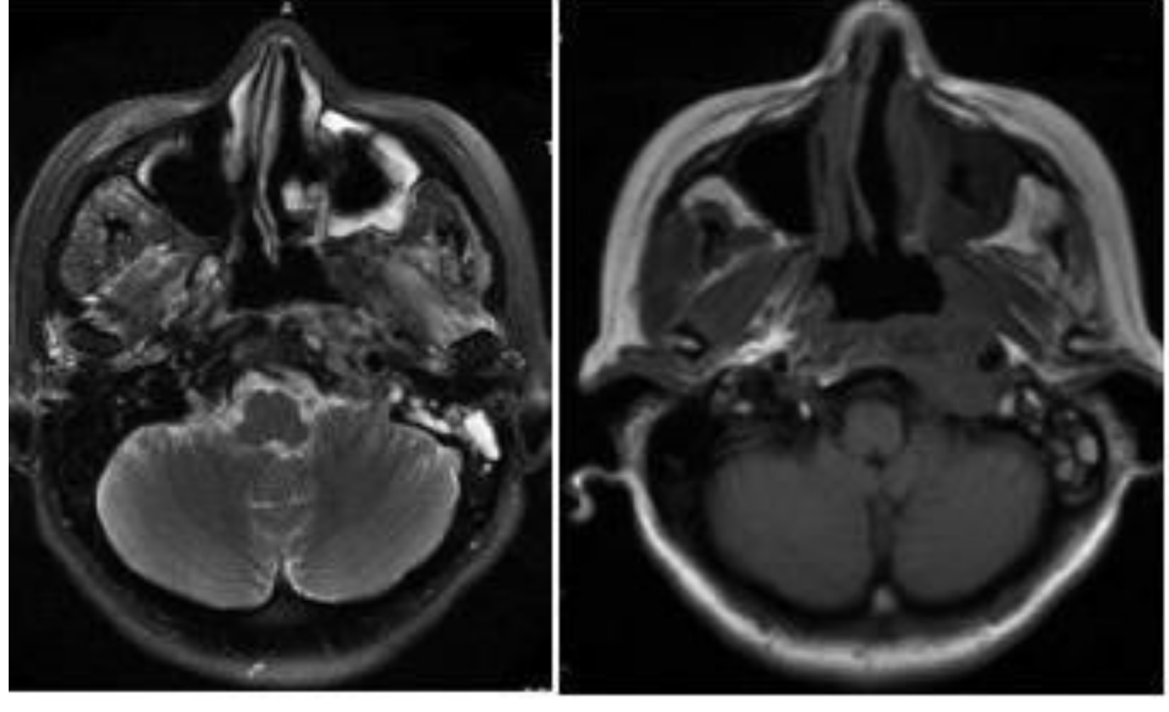

患者40+岁,女性,患者临床症状明显,近1年多来相继头痛、复视、肢体无力、吞咽困难等,当地医院诊断为较大斜坡脑膜瘤,辗转多地医院均告知肿瘤无法全切,术后并发症风险发生率高,后慕名咨询德国国际神经科学中心INI寻求巴特朗菲手术治疗,肿瘤切除97%以上,无相关手术并发症。

术前MR示:斜坡较大脑膜瘤,压迫脑干、颅神经,侵犯基底动脉等

术后MR显示:肿瘤近全切除,术后未见脑血肿、脑水肿,神经血管、脑干等组织保护完好。